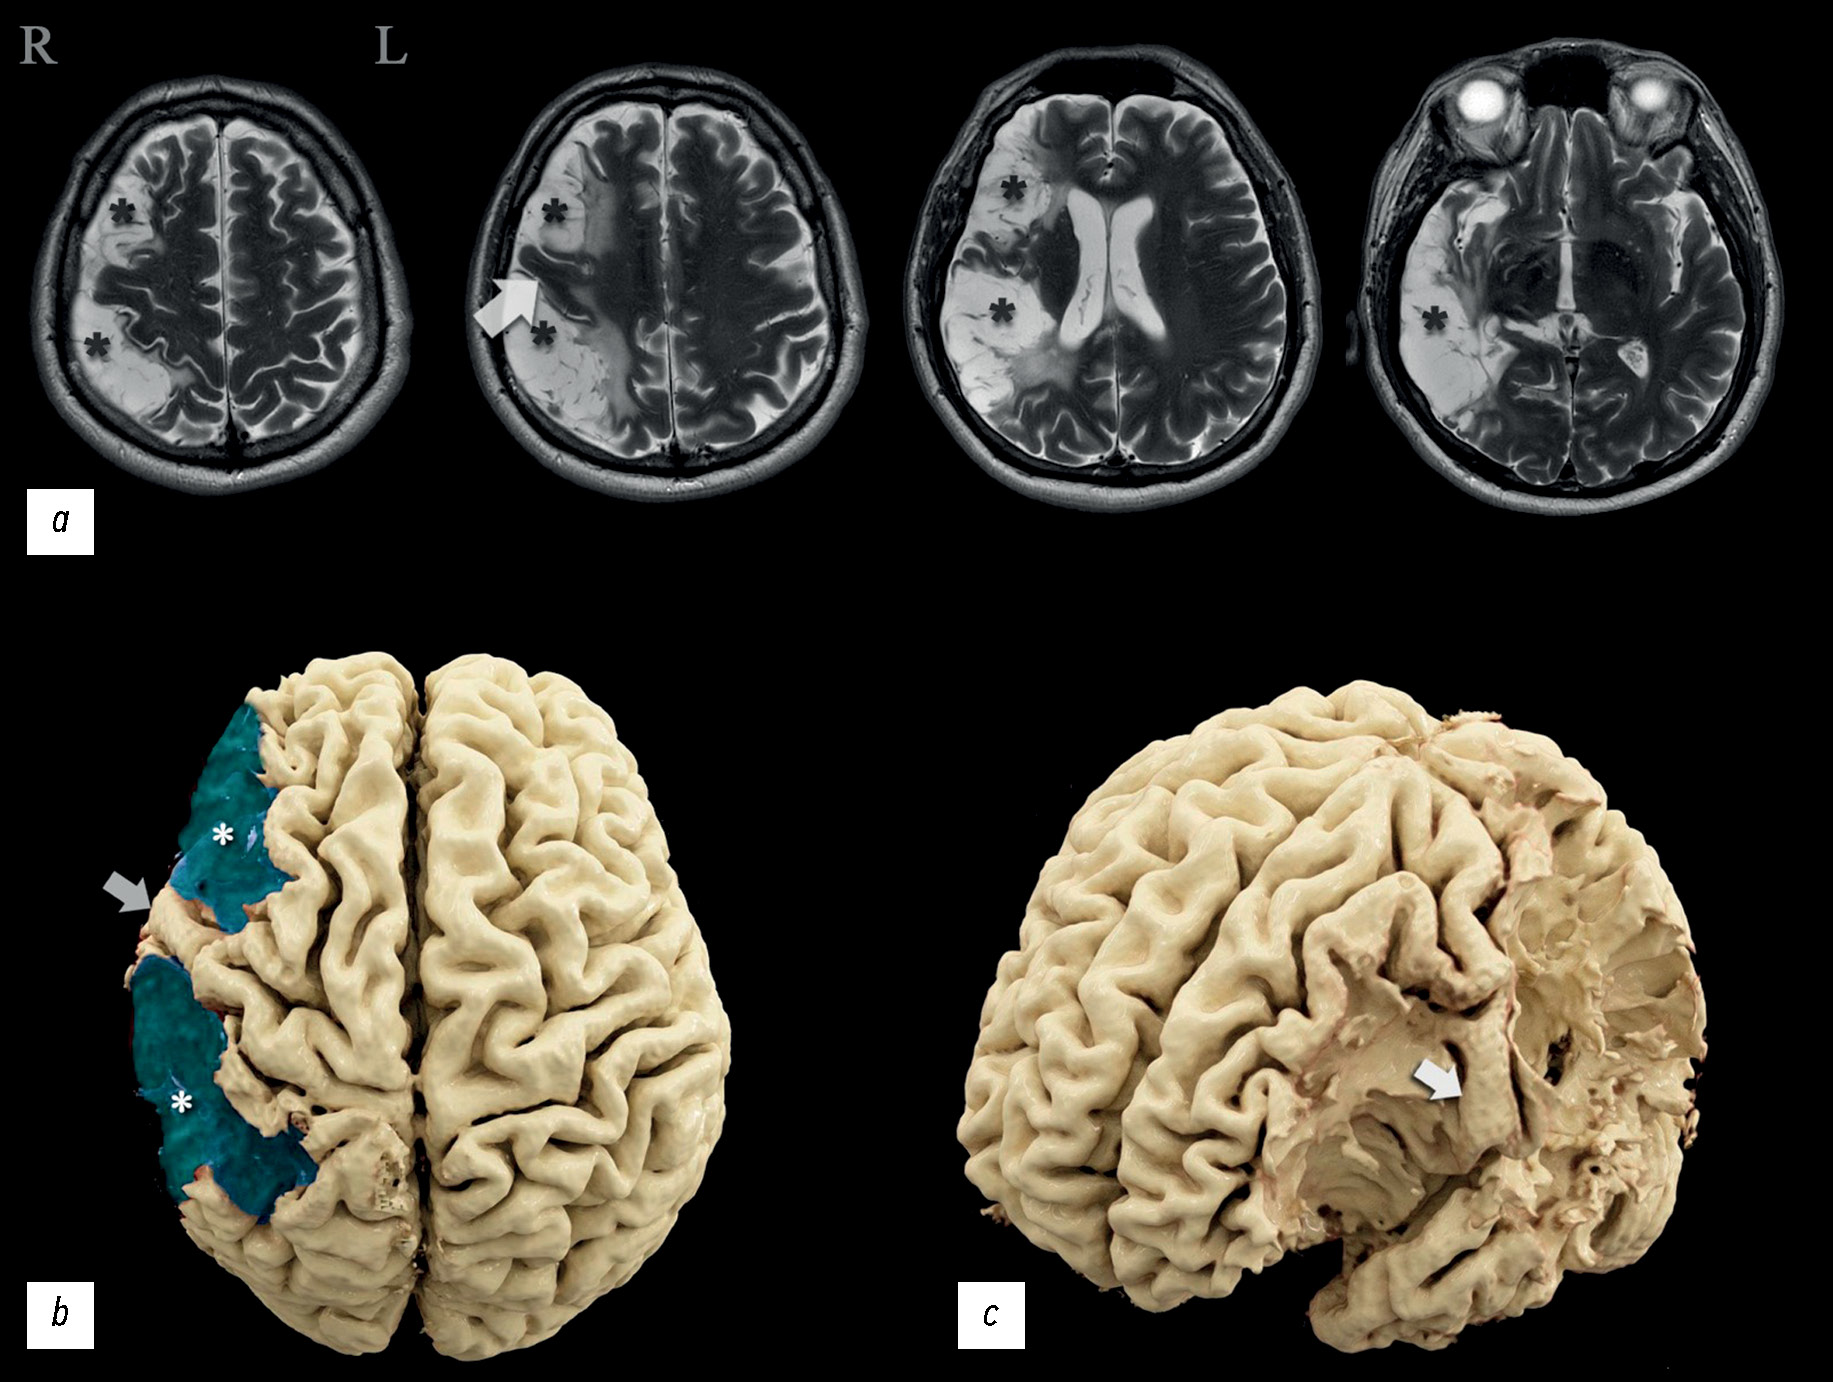

The severity of damage to different brain areas, including the cortex, can vary significantly in the associated neurologic deficit and reduction in the quality of life, often regardless of the lesion volume. The localization of the abnormalities plays a large part. Lesions of the dominant and subdominant hemispheres can differ greatly in both clinical features and effects on the patient’s quality of life. In this case report, a patient admitted for rehabilitation after two ischemic strokes underwent neurological and neuropsychological examination, complex instrumental diagnostics using electroencephalography, magnetic resonance imaging, computed tomography perfusion, magnetic resonance tractography, and functional magnetic resonance imaging. The patient had minimal left-sided hemiparesis, impaired regulation of voluntary activity, mild decrease in neurodynamic indicators, mildly impaired concentration, and a critical view of his condition. Neuroimaging findings demonstrated extensive postinfarction damage to the right subdominant hemisphere of the brain in the middle cerebral artery circulation. A nonconformity between the brain damage volume and the severity of its clinical signs was observed. Based on functional examination data, the dominant hemisphere was determined, and restructuring the functional centers was suggested. This clinical case was compared with similar ones, and their relationship with the data was analyzed. Information that expands the knowledge of the topography of the altered zones involved in motor and speech functions and the ability to perform arithmetic counting was obtained.